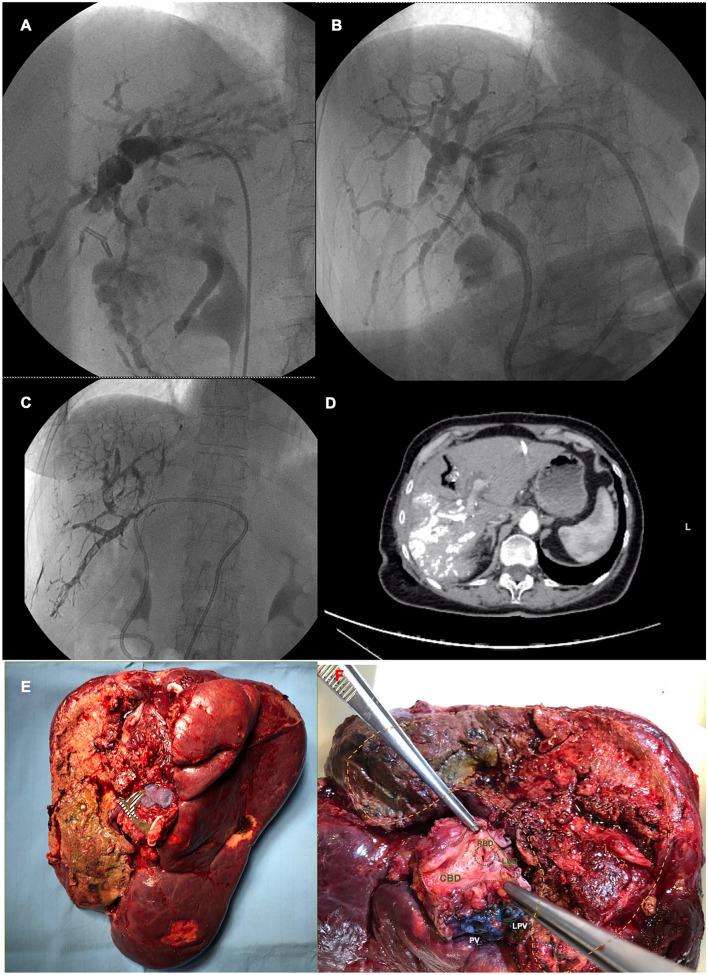

Perihilar cholangiocarcinoma (pCCA) is one of the most complex challenges for hepatobiliary surgeons. Poor results and high incidence of morbidity after Associating Liver Partition and Portal vein ligation for Staged hepatectomy (ALPPS) for pCCA discouraged this indication. It has been proposed that minimally invasive approach for ALPPS first stage, as well as combination of surgical liver partition and radiologic portal vein embolization (PVE), may improve outcomes reducing interstage morbidity. We report a case of right trisectionectomy with enbloc caudatectomy ALPPS scheduled for pCCA with robotic approach at stage-1, the full video is provided as supplementary material. Due to intraoperative presence of portal vein tumor infiltration during hilar dissection (no evidence in the pre-operative work-up), a radiologic right PVE was performed after stage-1 instead of portal vein ligation, followed by portal vein resection and biductal hepatico-jejunostomy at stage-2 with open approach. The patient was a 74-year-old female diagnosed with 3-cm mass-forming pCCA. The total clean liver volume was 1231 cc, with future liver remnant (FLR) volume of 25.1% (segments II and III). She was discharged in the interstage interval on postoperative day (POD) 4; CT scan on POD 12 showed that FLR increased up to 33% (369 cc) (Fig. 1). ALPPS was completed on POD 17, the postoperative course was uneventful, and the patient was discharged in good general condition on POD 19 after stage-2. Besides the already demonstrated advantages in terms of reduced interstage morbidity, robotic ALPPS represents a promising strategy to expand surgical indication in patients with pCCA. The combination of liver partition and PVE may increase the opportunities to perform radical resections in selected patients with pCCA and portal vein infiltration.

肝门部胆管癌(pCCA)是肝胆外科医生面临的最复杂挑战之一。由于 Associating Liver Partition and Portal vein ligation for Staged hepatectomy(ALPPS)治疗 pCCA 的效果不佳和发病率高,该手术不再适用于 pCCA。目前,有人提出 ALPPS 一期手术采用微创方法,联合手术性肝段分隔和放射学门静脉栓塞术(PVE),可能会降低手术间发病率,改善预后。我们报告了一例机器人辅助右三叶切除术联合尾状叶整块切除术的 ALPPS 治疗 pCCA 病例,一期手术采用机器人方法,完整视频作为补充材料提供。由于在肝门部解剖过程中发现门静脉肿瘤浸润(术前检查未见),因此在一期手术后进行了右 PVE,而不是门静脉结扎,然后在二期手术中采用开放方法进行门静脉切除和双胆管肝肠吻合术。患者为 74 岁女性,诊断为 3cm 肿块形成的 pCCA。总肝切除量为 1231cc,剩余肝体积(FLR)为 25.1%(II 段和 III 段)。患者在手术间间隔期间于术后第 4 天出院;术后第 12 天 CT 扫描显示 FLR 增加至 33%(369cc)(图 1)。ALPPS 于术后第 17 天完成,术后过程无并发症,患者在二期手术后第 19 天一般情况良好出院。除了已经证明的降低手术间发病率的优势外,机器人 ALPPS 为 pCCA 患者扩大手术适应证提供了一种很有前途的策略。肝段分隔联合 PVE 可能会增加对有门静脉浸润的选定 pCCA 患者进行根治性切除的机会。